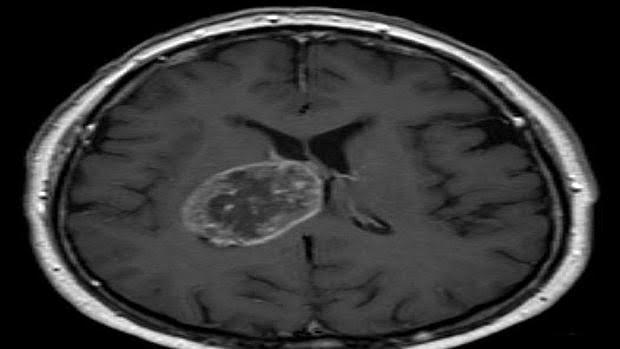

19/12/2017 19:41h. CÁNCER CEREBRAL Nueva terapia capaz de prolongar la supervivencia en el tumor cerebral más común M. LÓPEZ